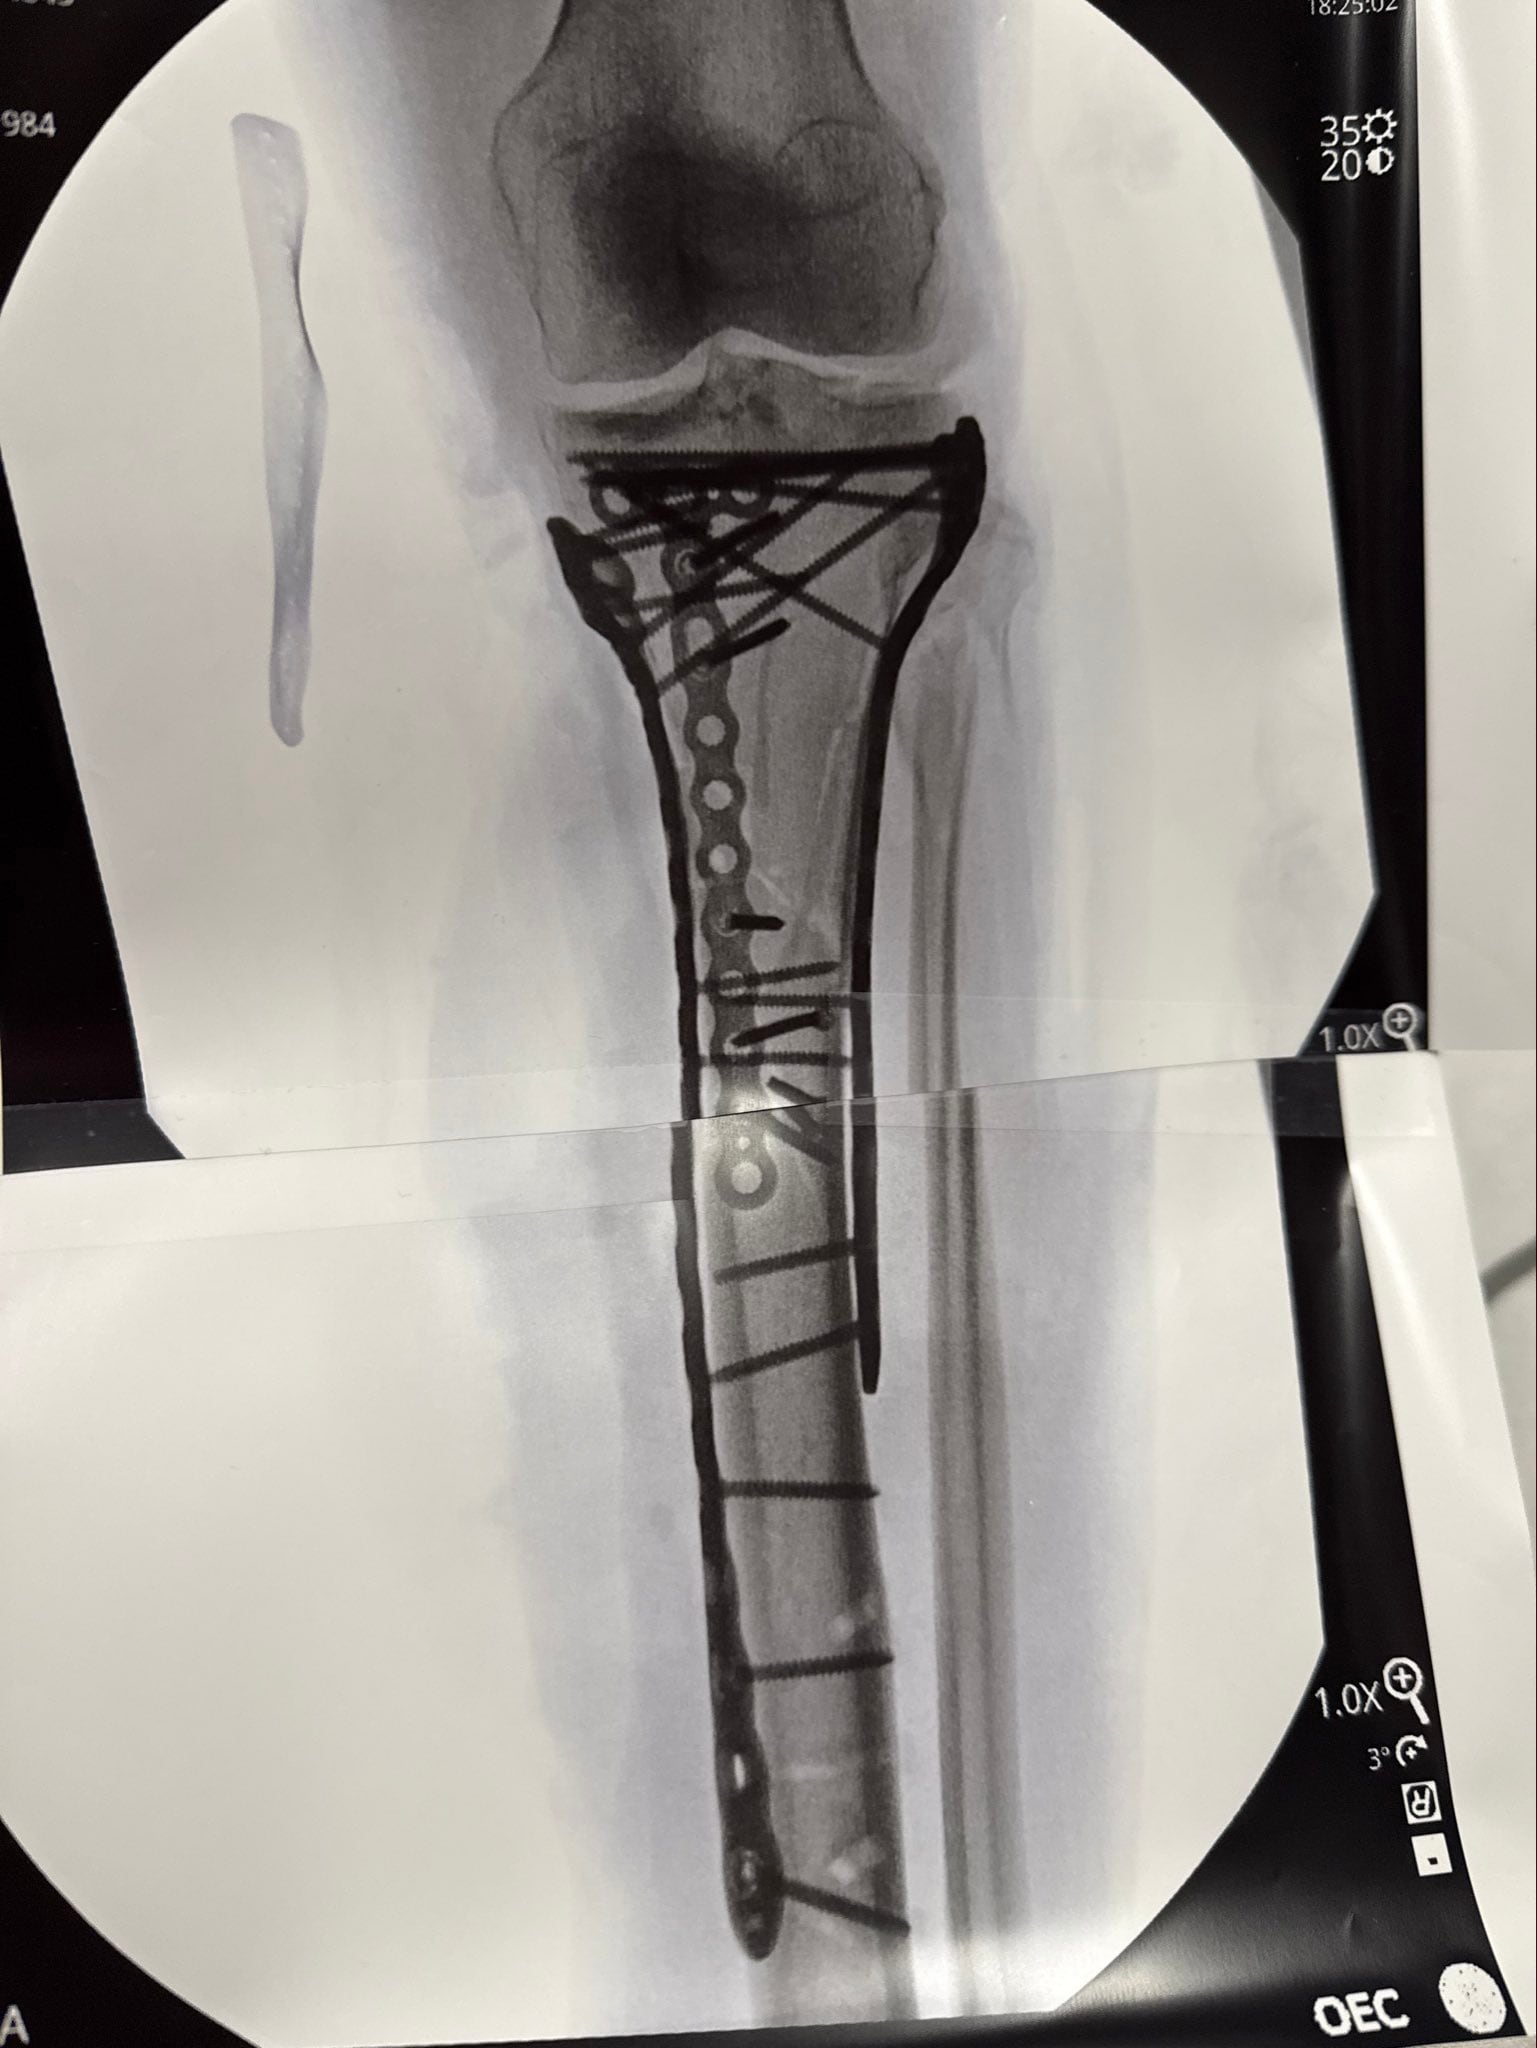

La recuperación de Lindsey Vonn tras el impacto sufrido en los Juegos Olímpicos de Invierno de Milano-Cortina reveló imágenes que parecen irreales: una radiografía de su pierna izquierda con varios tornillos metálicos y placas que ahora forman parte de su anatomía. La propia Vonn se refirió a su condición con ironía: “Soy biónica de verdad ahora”, expresó y subrayó el impacto físico y mental de esta etapa.

Ya en su perfil de Instagram, profundizó en sus sensaciones y lo acompañó de un video de ella en la camilla y una imagen de la radiografía en cuestión: “Como pueden ver han sido necesarias muchas placas y tornillos para recomponerlo todo. Debido a la gravedad del traumatismo, he tenido algunas dificultades después de la operación y aún no me han dado el alta del hospital… pero ya casi estoy lista. Pasito a pasito. Pronto explicaré la lesión y lo que significa todo esto”.

La mujer de 41 años fue sometida a cinco cirugías en menos de dos semanas, cuatro de ellas en Italia y una más en Estados Unidos tras lograr el alta médica y regresar a su país. La complejidad de la fractura en la tibia izquierda, combinada con el antecedente de múltiples lesiones previas y la existencia de implantes de titanio en su rodilla derecha, pone de relieve la magnitud de la situación. En palabras de la propia deportista: “Mi lesión fue mucho más severa que una simple fractura de pierna. Sigo asimilando lo que significa y el camino que tengo por delante”, escribió en redes sociales.

El doctor Bertrand Sonnery-Cottet, referente en ortopedia y cirugía de rodilla, advirtió en una entrevista con RMC Sports sobre el riesgo real que afrontan pacientes con lesiones tan graves: “Algunas lesiones como la suya pueden acabar en amputación”, aunque aclaró que el caso de Vonn no llegó a ese punto. El procedimiento más reciente, que duró más de seis horas, implicó la utilización de numerosas placas y tornillos para estabilizar la fractura. La atleta agradeció al equipo médico y relató que el dolor fue intenso, lo que dificulta su recuperación inmediata.